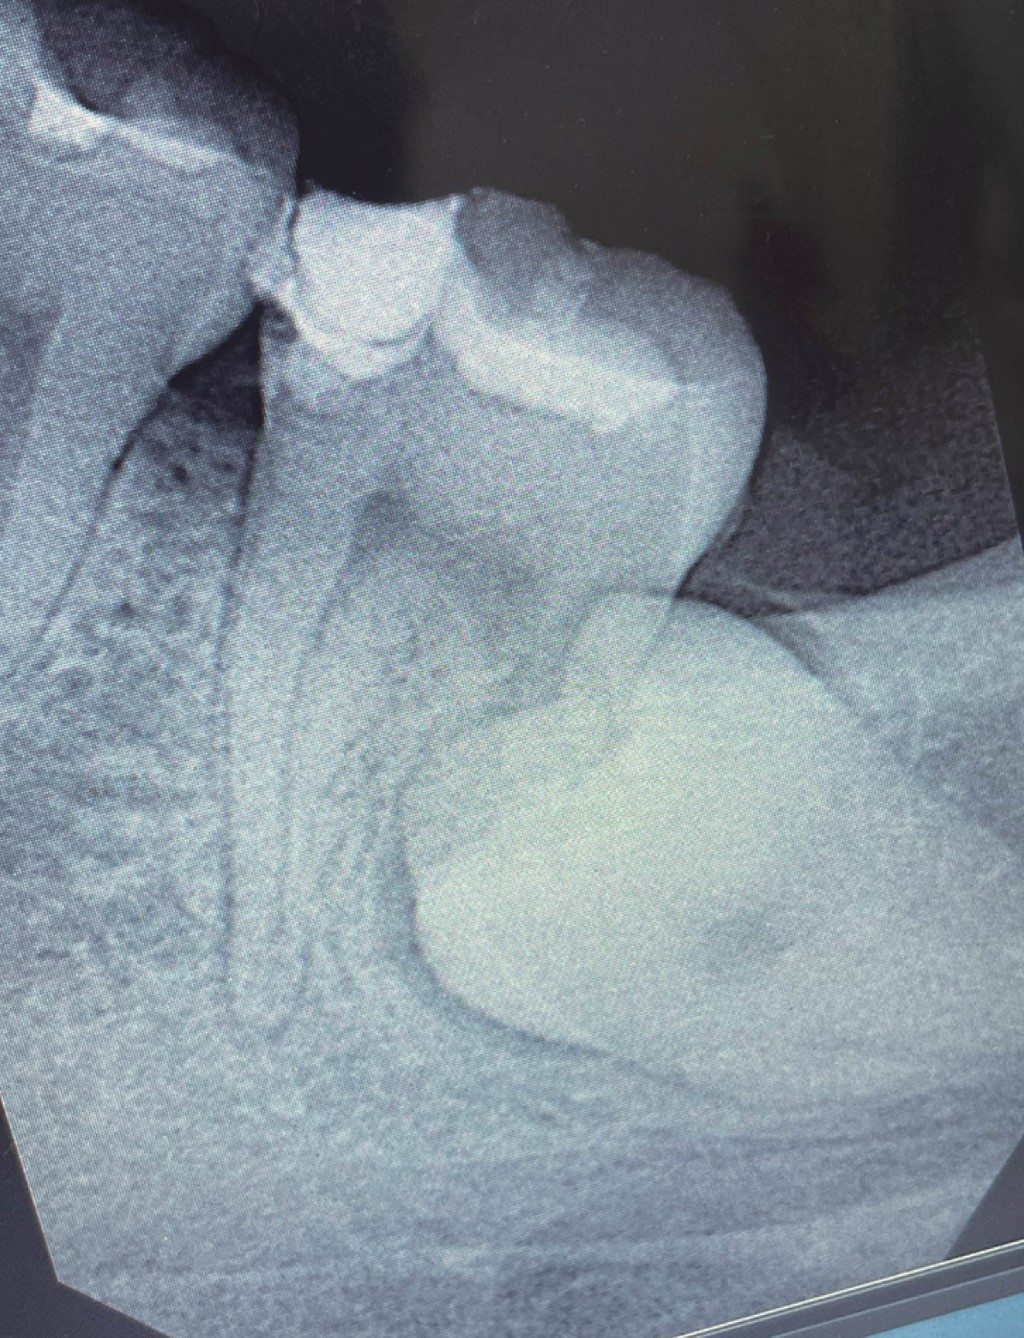

La radiografía muestra una superposición de imágenes entre la corona del tercer molar retenido y la raíz distal del segundo molar, que no permite observar la raíz distal del segundo molar.

La corona del segundo molar presenta zonas radiopacas en la corona en sus caras mesial y oclusal, presenta además una cámara pulpar amplia, es visible una línea radiolúcida en la raíz mesial, compatible con uno de los canales radiculares mesiales de tamaño delgado y con ligeras curvaturas hacia distal y mesial, también se observa una línea radiolúcida en la superficie mesial de la misma raíz, compatible con ensanchamiento ligero del espacio del ligamento periodontal, que se extiende hasta la zona periapical.

Se decide extraer el tercer molar, procedimiento que fue realizado por un cirujano maxilofacial, sin complicaciones aparentes. Después de tres semanas el paciente acude nuevamente refiriendo dolor en la zona del segundo molar izquierdo, se toma una nueva radiografía donde se observa pérdida de continuidad de la imagen del tercio medio y apical de la raíz distal (Figura 2).

Para finalizar, se colocó resina dual hasta rellenar completamente el acceso endodóncico y el paciente fue regresado con la cirujana dentista que lo refirió, quien le elaboró una restauración coronal completa de metal porcelana. A los seis meses el paciente acude para control radiográfico, refiriendo haber estado asintomático durante este tiempo, podemos observar ausencia de zonas radiolúcidas periapicales, nivel del hueso alveolar satisfactorio, sin aumento del espacio del ligamento periodontal, (Figura 14), por lo que se decide citarlo en un año para nuevo control.

Figura 1

Figura 2

Figura 14